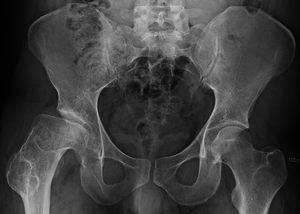

X-rays of the hip may suggest and/or verify the diagnosis. X-rays usually demonstrate a flattened, and later fragmented, femoral head. A bone scan or MRI may be useful in making the diagnosis in those cases where X-rays are inconclusive. Usually, plain radiographic changes are delayed 6 weeks or more from clinical onset, so bone scintigraphy and MRI are done for early diagnosis. MRI results are more accurate, i.e. 97 to 99% against 88 to 93% in plain radiography. If MRI or bone scans are necessary, a positive diagnosis relies upon patchy areas of vascularity to the capital femoral epiphysis (the developing femoral head).